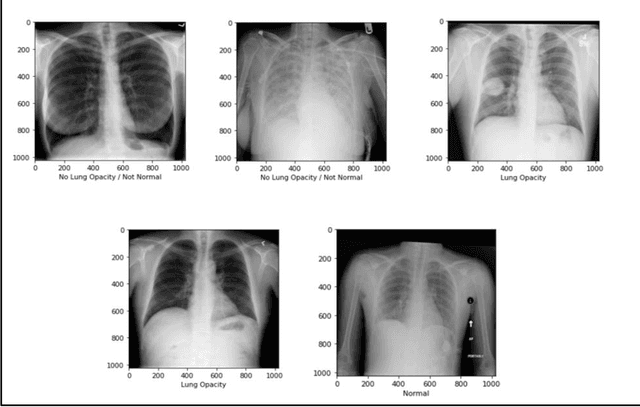

Abstract:With the advancement in AI, deep learning techniques are widely used to design robust classification models in several areas such as medical diagnosis tasks in which it achieves good performance. In this paper, we have proposed the CNN model (Convolutional Neural Network) for the classification of Chest X-ray images for Radiological Society of North America Pneumonia (RSNA) datasets. The study also tries to achieve the same RSNA benchmark results using the limited computational resources by trying out various approaches to the methodologies that have been implemented in recent years. The proposed method is based on a non-complex CNN and the use of transfer learning algorithms like Xception, InceptionV3/V4, EfficientNetB7. Along with this, the study also tries to achieve the same RSNA benchmark results using the limited computational resources by trying out various approaches to the methodologies that have been implemented in recent years. The RSNA benchmark MAP score is 0.25, but using the Mask RCNN model on a stratified sample of 3017 along with image augmentation gave a MAP score of 0.15. Meanwhile, the YoloV3 without any hyperparameter tuning gave the MAP score of 0.32 but still, the loss keeps decreasing. Running the model for a greater number of iterations can give better results.